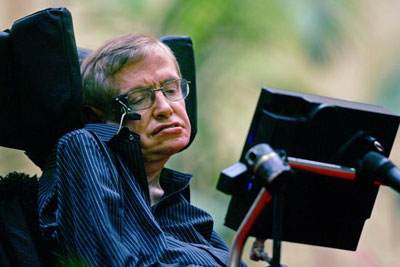

علت مرگ بیشتر مبتلایان به ALS ناتوانی در تنفس یا عفونت ریههاست. شاید جالب باشد بدانید یک استثنای عجیب بر قاعده سالهای زندگی پس از ابتلا به ALS وجود دارد و در حال حاضر هم زنده است و اتفاقا جزو نوابع نادر در تاریخ علم بشر نیز به شمار میرود.

استفن هاوکینگ، فیزیکدان و کیهانشناس برجسته بریتانیایی، از سال 1963، یعنی از 21 سالگی که نخستین علائم بیماریاش بروز کرده تا الان (چیزی حدود 51 سال) با این بیماری زندگی میکند و هر چند تقریبا به لحاظ جسمانی کاملا ناتوان است، قوای ذهنیاش همچنان نبوغآمیز به فعالیت ادامه میدهند.

ALS در نهایت بر ماهیچههایی که مسئولیت تنفس، بلع و سایر فعالیتهای حیاتی بدن را به عهده دارند تاثیر میگذارد و در نتیجه، سرانجام به مرگ منجر خواهد شد، اما فراموش نکنیم که پژوهشهای بسیاری برای یافتن علت و درمان این بیماری همچنان در جریان است و نیز این را هم فراموش نکنیم که استثنا ممکن است برای هر فرد دیگری غیر از هاوکینگ هم رخ دهد.